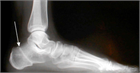

1. 分類は、変形のステージとタイプ分けからなる([1]。ステージは、足変形に可撓性があればⅠ、なければIIとする。変形のタイプはクラスAからクラスEの5つに細分され、クラスは単独あるいは複合することもある(表記例:ⅠA、IIABCIEなど)。(*日本足の外科学会用語委員会による和名)